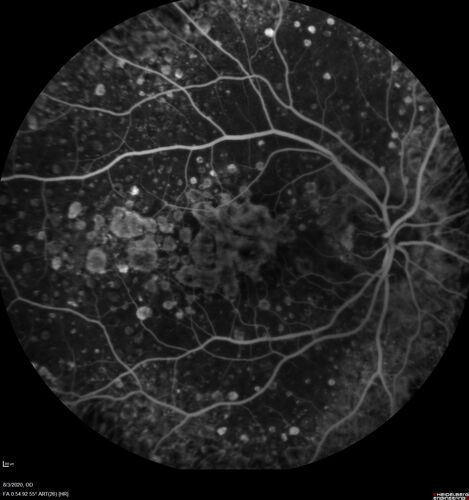

Dry AMD geographic atrophy and cystoid macular edema

79 year old vision is in for a checkup with no visual complaints in the left eye.  This is her better eye.  VA 20/200 OD, 20/50 OS.  3 years ago she had a CRVO in the left eye.  She is also diabetic for 20 years, has carotid insufficiency and anemia.  Left eye shows CME.  This was not treated and the vision improved to 20/40 over the next year although mild edema persisted.